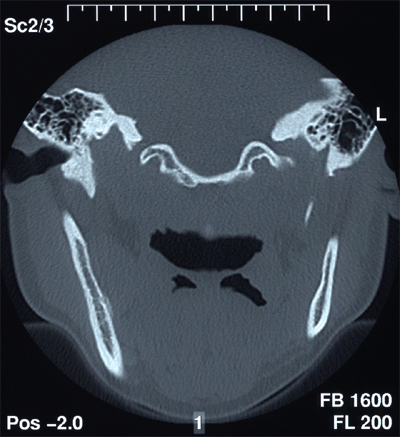

Die operativen Methoden erfordern, dass alle diese Probleme bei und in der Praxis unter erhöhten Hygienemassnahmen durchgeführt werden. Das Schwergewicht der allgemeinen zahnärztlichen chirurgischen Eingriffe liegt wohl in der Entfernung verlagerter Zähne, speziell der Weisheitszähne im Unterkiefer. Liegt der verlagerte Weisheitszahn so tief im Knochen, dass seine Wurzeln bis zum Teil an den Unterkieferrand reichen, lassen wir vorgängig der Operation ein sogenanntes CT (Computer-Tomogramm) erstellen, das uns die dritte, räumliche Dimension zum Verlauf der sensiblen Nerven im Unterkiefer zu den Wurzeln des Weisheitszahnes darstellt. Je nachdem, wo dieser Nerv verläuft, wird die Kraft zur Entfernung des Weisheitszahnes an verschiedenen Ansatzpunkten eingesetzt.

Abb. 1 zeigt das klinische Bild vor der Aufklappung. Der Pfeil markiert die Stelle, wo der Weisheitszahn unter der Schleimhaut im Knochen liegt. Vor der Operation musste ein CT zur transversalen Lagebeurteilung des sensiblen, wichtigen Lippennerves zur Wurzelspitze des Zahnes angefertigt werden. In der CT-Schichtaufnahme von Abb. 2 wird ersichtlich, dass der Weisheitszahn sehr tief unten liegt.